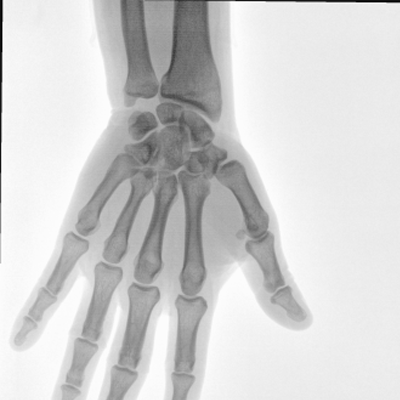

大尺寸動(dòng)態(tài)平板探測(cè)器,高DQE、低噪聲、圖像清晰。采用多分辨率圖像增強(qiáng)處理技術(shù),不同部位不同圖像處理算法,滿足客戶多樣化的需求。

采用智能變頻脈沖透視技術(shù),優(yōu)化圖像質(zhì)量的同時(shí)降低輻射劑量,呵護(hù)醫(yī)患健康